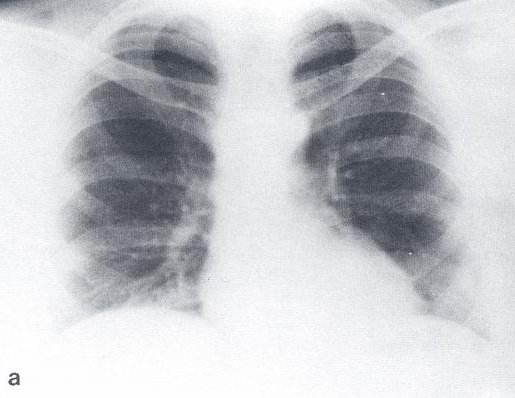

His past medical history was significant for an episode of urolithiasis with spontaneous passage of the stone, and mild hypertension treated with a beta-blocker. He had no childhood history of respiratory disease or chest trauma and was a lifelong non-smoker. Chest X-Ray taken for tuberculosis screening at age 29 years (Figure 1) was unremarkable. There was no family history of interstitial and other lung disease.

Figure 1: Chest X-ray 19 years prior to presentation